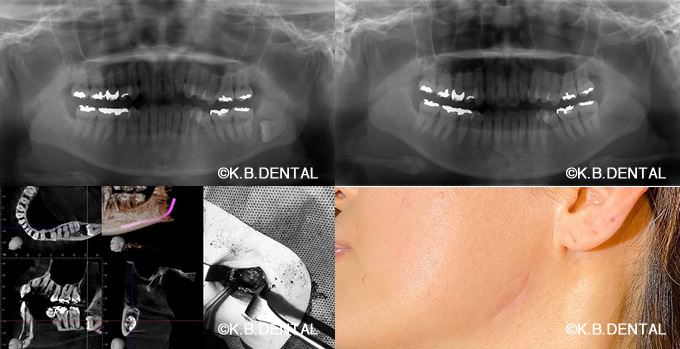

術後2年経過の最も典型的なエナメル上皮種です。再発率が非常に高いので最低でも5年以上の経過観察が必要となります。今回は摘出術と一部健常域まで辺縁切除(骨を削る)を行いました。

1枚目(パノラマ)上:術前 下:術後 摘出部分に新生骨を認めます。

2枚目(CT)上:術前 下:術後 摘出部分に新生骨を認めます。

3枚目 左:摘出物の腫瘍本体と割断像 右:割断して内容物が充実性である事がわかります。

4枚目 上:高倍率 下:低倍率 腫瘍実質の胞巣が濾胞状を示しているのがわかります。